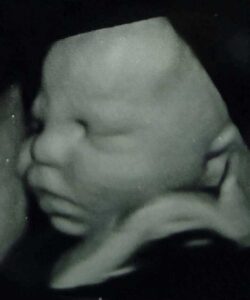

My mind was like ‘just do it so you can throw it away and close this part of your life.’ To my surprise it was positive. I had such a mix of happy and scared emotions. We decided this time we would wait to tell ANYONE. Having to tell family and friends about a loss is so painful. With our son’s 3rd birthday coming we thought it would be great if we announced at his party AND knew the gender! How fun would that be?! So I signed up for the maternit21 test. After all, it’s just a simple blood test.

Waiting for those results seemed like a lifetime. We were 2 days shy of 12 weeks so we told the whole family, and told them we would know the gender soon. Little did we know when that call came, it would not be what we expected. ‘Positive for T21,’ I heard the doctor say. I had no idea what that meant so she told me he would likely have Down syndrome. There was a high percentage chance of miscarriage, a high risk for stillborn, and of course the risk of many health issues. I sobbed right there on the phone. I love my doctor and she was such a positive support during all of this.